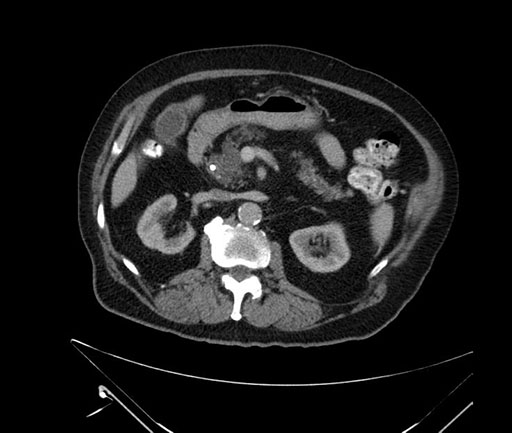

Imaging Analysis

Look through the patient's CT scan to identify any areas of concern for the necessary procedure.

Based on your CT findings, which issue(s) would give reason for "planned slowing down moment(s)" in this case?